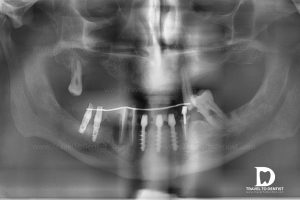

Avec la perte de dents, la mâchoire souffre de modifications de volume. Si vous avez décidé de mettre des implants, votre médecin commencera par une investigation sur la quantité d’os disponible. En fonction de ses calculs, il pourrait trouver une condition osseuse minimale pour l’insertion des implants. Le minimum est indiqué par la taille des implants que le médecin a décidé d’utiliser et diffère selon la mâchoire dentaire et la région de la dent à remplacer. Si vous avez une base osseuse minimale, ça ne vous oblige pas a porter les prothèses amovibles, qui pourraient vous mettre mal à l’aise.

On va expliquer ci-dessous les avantages et les inconvénients des deux possibilités. Pour diverses raisons, certains médecins proposeront la première option tandis que d’autres spécialistes pourront conseiller la deuxième. C’est pourquoi, sur la base de la même radiographie, un même patient pourrait recevoir de différents devis lors de la recherche d’une clinique dentaire pour vous soigner les dents. L’objectif que nous avons exposé dans cet article est de vous faire comprendre tout d’abord la situation dans laquelle vous vous trouvez et les alternatives existantes avec leurs spécificités, et la décision qu’elle soit prise par vous-même compte tenant de la multitude de facteurs externes qui pourraient influencer plus ou moins l’alternative choisie (les exigences concernant la quantité de dents que vous voulez avoir sur chaque mâchoire, le résultat esthétique, l’âge, l’état de santé, l’hygiène, le temps proposé pour finir les soins, le budget).